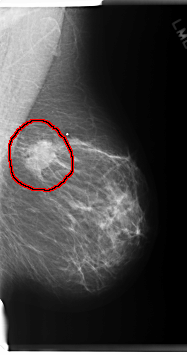

C_0220_1.RIGHT_MLO

LEFT_MLO LINES 6032 PIXELS_PER_LINE 3176 BITS_PER_PIXEL 12 RESOLUTION 50 OVERLAY

FILE: C_0220_1.LEFT_MLO.OVERLAY

TOTAL_ABNORMALITIES 1

ABNORMALITY 1

LESION_TYPE CALCIFICATION TYPE AMORPHOUS DISTRIBUTION CLUSTERED

LESION_TYPE MASS SHAPE IRREGULAR MARGINS MICROLOBULATED

ASSESSMENT 5

SUBTLETY 5

PATHOLOGY MALIGNANT

TOTAL_OUTLINES 1

BOUNDARY